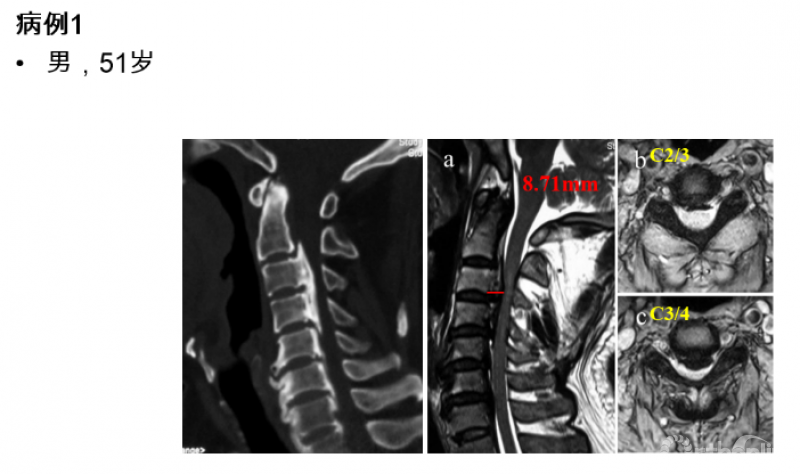

在初步了解颈后路减压手术后脊髓的运动规律及影响因素之后,我们对于如何制定合理的纵向减压范围又做了进一步的研究,初衷是解决临床工作中遇到的一类的临床问题。下面以具有代表性的临床病例进行说明。

图1

从该患者的影像资料可以发现以下特点:致压物主要是来自于脊髓前方的后纵韧带骨化块,造成脊髓腹侧受压。在颈2/3间隙及以上水平,并未造成脊髓明显压迫,但在C3/4间隙水平椎管侵占率陡然增大,是脊髓受压最严重的节段。在这种情况下,颈后路纵向减压范围应该是C3-7、C2-7或者C1-7?

实际上,类似于病例1的情况并不少见,尤其多见于后纵韧带骨化症的患者,暂且不对例1的治疗方案做出决定,我们来看另一例给我们启示的病例:

图2

对于该例患者,C2/3间隙水平有轻度脊髓压迫,脊髓受压最重的节段仍然在C3/4水平。我们进行了再次手术,并向头侧扩大减压范围至C2,术后不仅C2/3水平的轻微压迫得到解除,C3/4水平脊髓压迫也明显去除了(图3),神经功能改善。

这个病例给我们的启示是:扩大减压范围至C2,有助于提高C3/4水平脊髓减压的效果。然而,显然并不是所有患者都需要扩大减压,那么需要回答的问题是:C3/4水平的脊髓前方致压物多大,需要扩大减压范围至C2?

图3 术后核磁显示脊髓减压充分

我们对57例患者的资料进行回顾,按减压节段分为C3-7组(n=32)和C2-7组(n=25)。测量并比较两组患者术后核磁上C2/3至C7/T1各节段脊髓前方至椎体后缘的距离(图4,在本研究中命名为脊髓前间隙,Anterior cord space, ACS),以了解不同的减压范围下减压效果的差异,以及将减压范围扩大至C2能带来的脊髓减压效果的获益究竟有多大。从而回答上述临床问题。

图4

本研究的结果提示,扩大减压范围至C2后,不仅使C2/3水平ACS增加,其相邻的C3/4水平ACS亦有明显增加,提高了C3/4水平避让前方压迫的能力(图5)。

图5

从数值上进行分析可以发现:C3-7组C3/4水平ACS均值6.60mm(95%CI:6.10~7.11),当该水平致压物中矢径>6.10mm时,C3-7减压即可能在C3/4水平残留压迫,当C3/4水平致压物中矢径>7.11mm时,C3-7减压则几乎不能充分解除压迫;如果扩大减压范围至C2,C3/4水平的ACS平均可达8.74mm(95%CI:8.10~9.38),最大可避让中矢径为9.38mm的前方致压物(图6)。

图6

此外,C4-5及以下节段未受C2减压的影响,提示当目标节段及其相邻节段的椎管充分扩大后,该目标节段即获得最大减压效应,而不会受到远隔节段是否减压的影响,亦即颈椎后路减压的效应主要受局部因素(局部硬膜囊膨起及局部曲度)的影响,这与系列一的研究结果是一致的。

最后,我们回到病例一,利用上述研究结果指导临床决策:C3/4水平致压物中矢径8.71mm>7.1mm,所以C3-7减压势必残留压迫,应选择C2-7减压,术后获得了9.34mm的ACS,充分解除了脊髓压迫(图7)。

图7